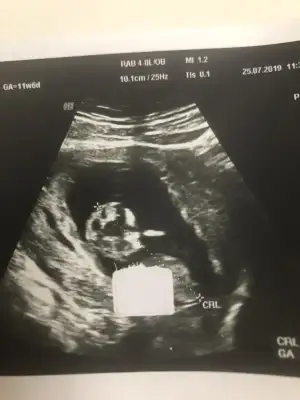

Tamam kız bu bebiş.kesin kızEki Görüntüle 2294615 Eki Görüntüle 2294617

Bunlarda az önce alınan resimler normalde 11 hafta 6 günlük ama usg de 12 hafta 6 günlük

Kızlaar bende çok merak ediyorum geçen hafta 11+5 ken bunlar İpucu veriyormu sizce cinsiyet nedir?